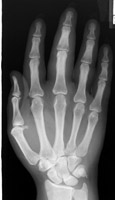

X-ray of the hand with diffuse fusiform soft-tissue swelling of the entire 3rd digit. This sign refers to fusiform soft-tissue swelling involving an entire, single digit within the hand. The appearance of a sausage digit (cocktail sausage) is classically associated with the single-ray pattern of involvement seen in some patients with psoriatic arthritis, and may be the initial manifestation of the disease.

PA hand - Click on the image for a larger version